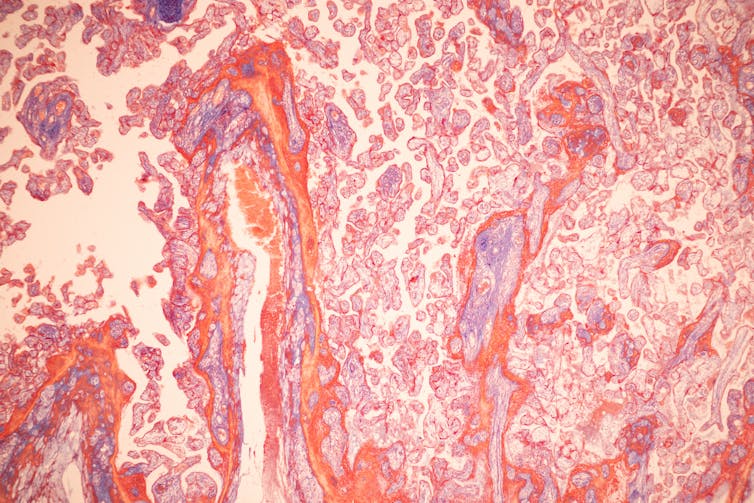

The placenta is an organ created during pregnancy that provides nutrients to a growing fetus through an umbilical cord. It’s usually large and relatively flat, composed of blood vessels, stem and immune cells, and collagen. It doesn’t look particularly appetizing to most people, and those who have eaten placentas often mention an unpleasant taste or smell.

Researchers have been exploring recycling placentas, which are often thrown away after delivery, as a type of biomaterial to regrow wounded tissue in patients. Because the placenta is rich in nutrients and stem cells that give it antimicrobial, anti-inflammatory and pro-regenerative properties, this organ is a particularly good candidate for medical applications.

I have used human placentas in my own research to study how they work in a variety of wound repair scenarios. I can take a volunteer patient’s donated placenta and remove factors that may negatively affect healing, such as all cells, blood and other components that may cause inflammation. Then I can take the material that’s left – primarily containing essential growth nutrients and the tissue foundation that cells used to live in – and use it to improve bone or tendon repair.